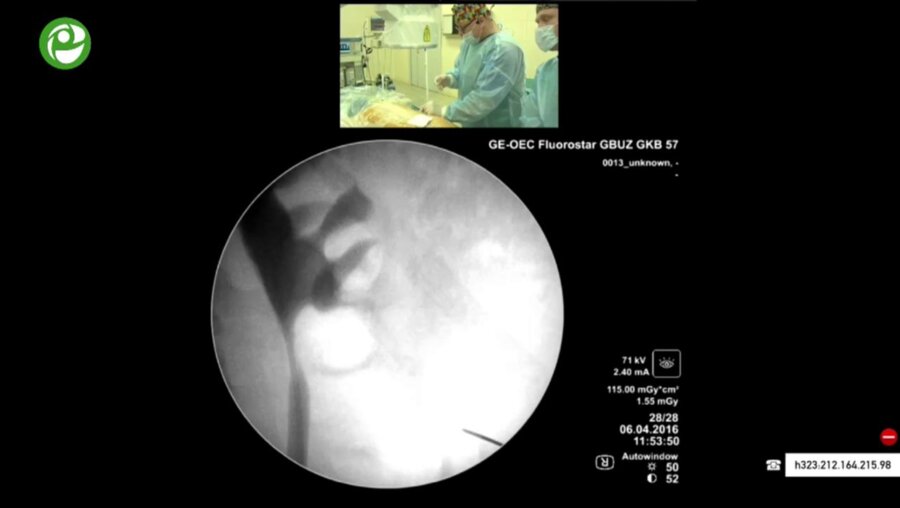

Мастер-класс по перкутанному лечению камней почки

06 апр 2016

3094 просмотра